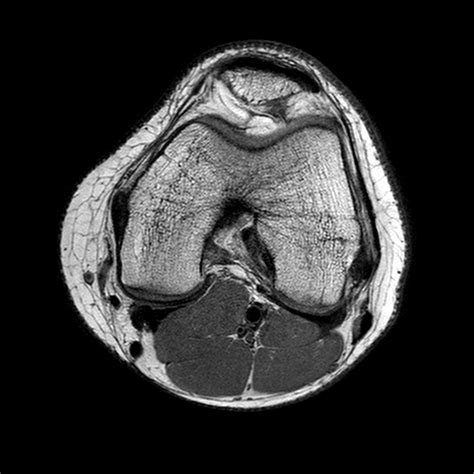

Interpreting the results of a Normal Knee MRI requires a trained radiologist. The images will be reviewed to identify any abnormalities. Here are some key structures that are typically examined:

Bones

The MRI will show the bones of the knee, including the femur, tibia, and patella. Any fractures, tumors, or other bone abnormalities will be visible.

Cartilage

Cartilage is the smooth, slippery tissue that covers the ends of bones and allows them to move smoothly against each other. The MRI can detect tears or wear and tear in the cartilage, which is common in conditions like osteoarthritis.

Menisci

The menisci are C-shaped pieces of cartilage that act as shock absorbers between the femur and tibia. The MRI can show tears or degeneration in the menisci, which are common in athletes and older adults.

• normal knee mri axial